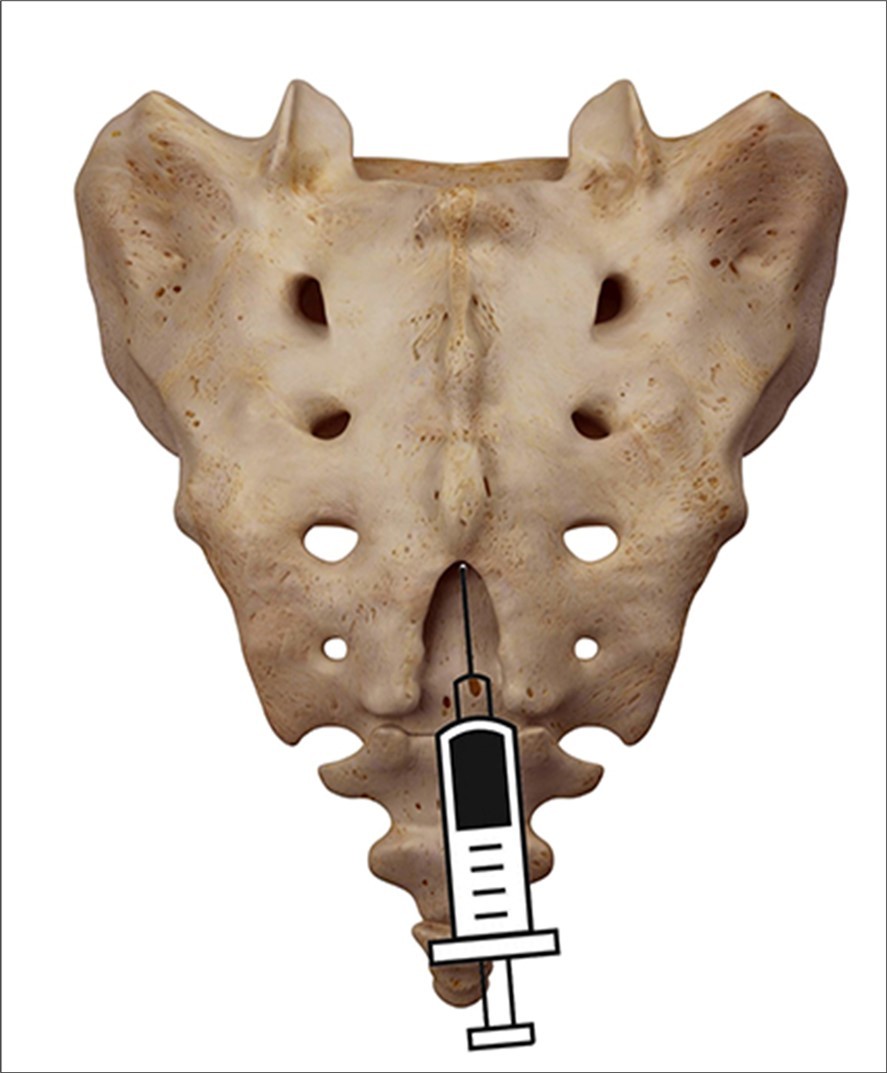

sacral injection involves injecting a steroid medication into the epidural space (Figure 1), which is the area around the spinal nerves. A caudal injection can help treat various conditions that cause nerve pain, such as herniated discs, spinal stenosis, sciatica, and post-surgery syndrome.

Figure 1.posterior view of the injection in the hiatus.